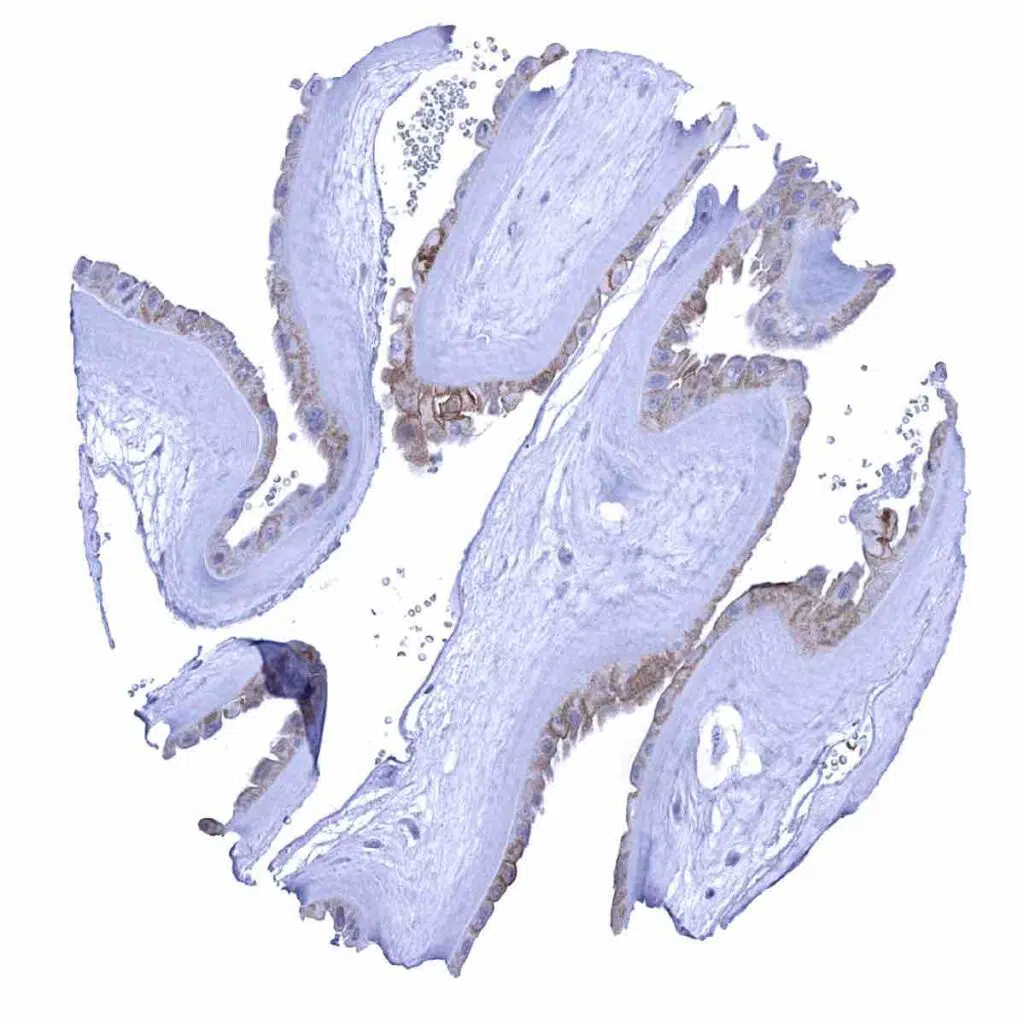

Tonsil – Moderate to strong desmoglein 1 immunostaining of a fraction of squamous epithelial cells in tonsil crypt epithelium

Tonsil, surface epithelium – Weak to moderate membranous desmoglein 1 immunostaining of the squamous epithelium. The staining is least intensive in the basal cell layers